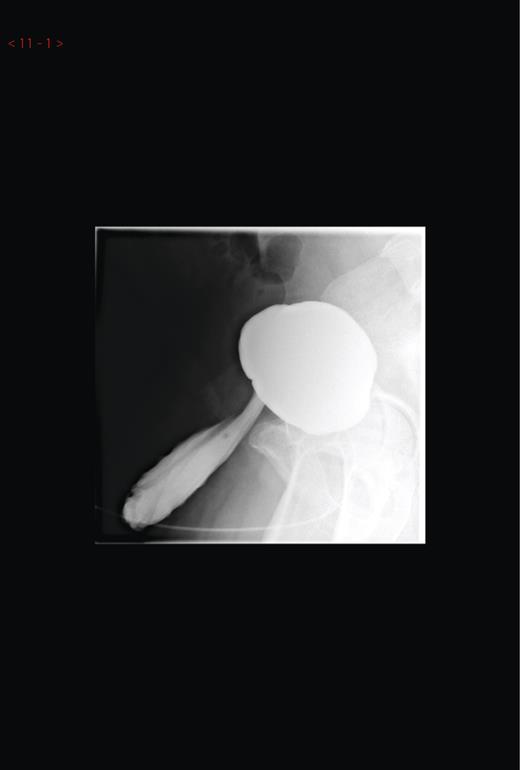

Based on this cystoscopic finding, a micturating cytogram was arranged to evaluate this diverticulum as seen in the figures provided (Figures 1 and 2). This showed an unusual huge bladder diverticulum that had herniated through his inguinal canal, filling his left hemiscrotum.

Micturating cystourethrogram showing contrast in the left hemiscrotum.